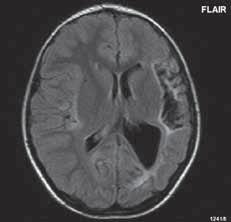

Základním cílem zobrazovacích metod je vyloučení ostatních, nenádorových, někdy expanzivních procesů (abscesu, vstřebávajícího se hematomu, různých typů cyst…), která mají zpravidla jiné klinické vedení. Při zobrazení nádorů bychom se měli snažit zodpovědět tři základní otázky, charakterizující tumor:

1. typing – odlišení nenádorových patologických procesů a snaha o histologickou klasifikaci tumoru.

2. staging – hodnotí stupeň pokročilosti růstu nádoru, kde kromě radiologického nálezu je nutné vzít v úvahu i neurologické a histologické vyšetření.

3. grading – určení stupně vyzrálosti nádoru, stupeň malignity (četnost mitóz, jaderná atypie, angiogeneze, nekrózy).